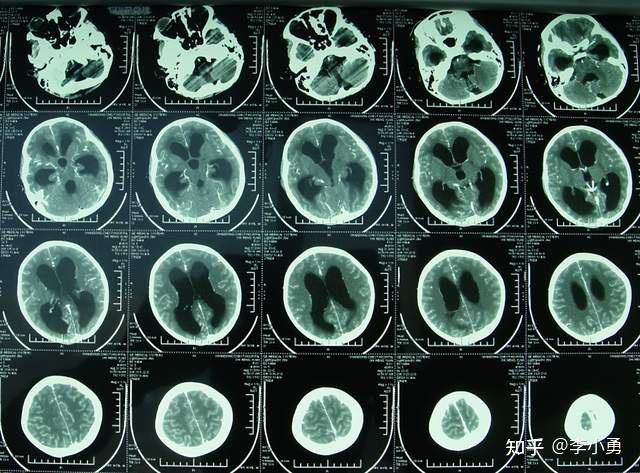

近致命性结核脑膜炎性脑积水发病后2个月内先后经4家医院治后仍无改善

10岁女孩重度结核脑膜炎性脑积水被多家医院告知没有办法治了但经李小